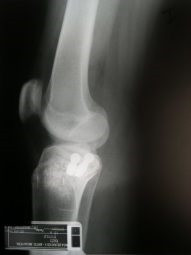

Fractura de plato tibial reducida bajo control artroscópico

Envíado por Dr. Luis Rodolfo Morales Choto